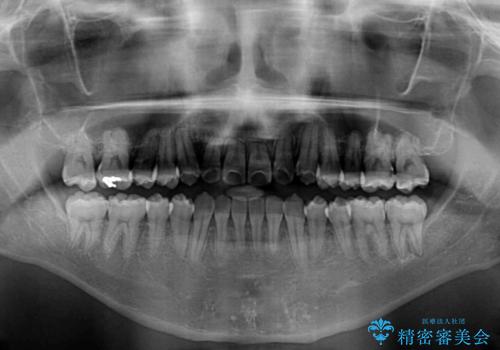

左右の八重歯が気になる ワイヤー装置での咬み合わせ改善

- 八重歯と前歯のデコボコを気にして来院された患者様です。

営業職であり、商談などで飲食をする機会が多いとのことで、インビザラインではなく、ワイヤー装置にて矯正治療を行うこととしました。

舌の突出癖がなかなか改善されず、上下前歯部の接触が得られるまでに予定の倍ほどの期間がかかりました。